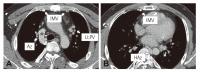

Total absence of superior vena cava (SVC) is a very rare anomaly, and the patient usually suffers from SVC syndrome or conduction disturbances. We report an asymptomatic 27 year-old male, with complete absence of SVC. Transthoracic echocardiography and computed tomography demonstrated the absence of SVC and other congenital cardiac anomalies, but the presence of prominent collateral vessels that allow a sufficient venous return.